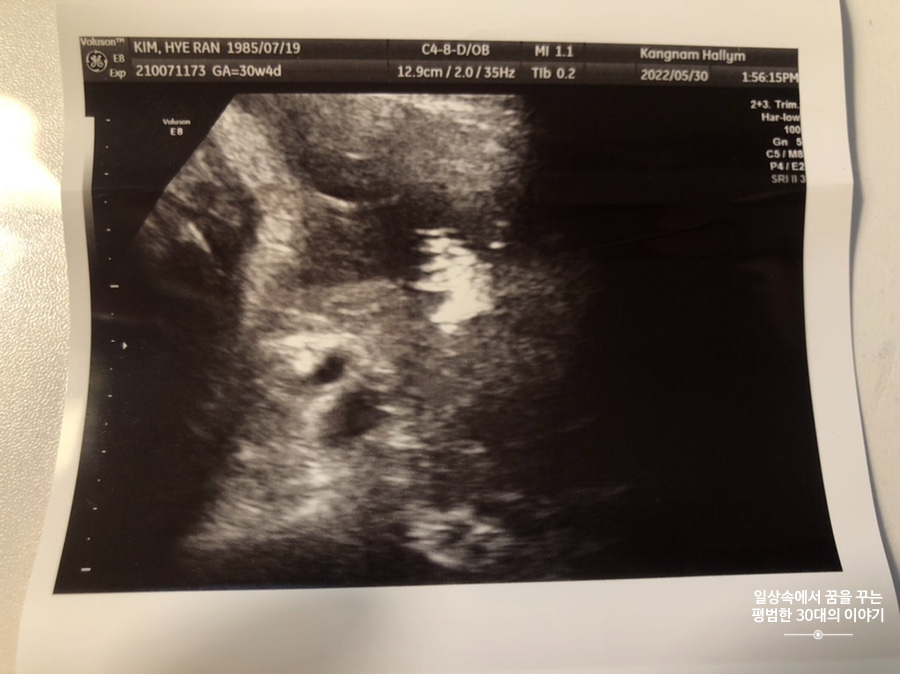

5월 30일 월요일(30주차 4일)

BPD(Biparietal Diameter, 위에서 볼 때 태아 머리 단면의 가장 긴 길이): 7.81cm

HC(Head Circumference, 태아 머리둘레): 28.57cm

AC(Abdominal Circumference, 배 둘레): 27.48cm

EDD(Expected Date of Delivery, 출산 예정일): 2022년 8월 4일

FL(Femur Length, 허벅지뼈 길이): 5.83cm

GA(Gestational Age, 임신 주차): 30주차 4일

EFW(Estimated Fatal Weight, 태아 예상 체중)=EBW(Estimated Body Weight): 1735g

FHR(Fetal Heart Rate, 심장박동 수): 142bpm

CL(Cervical Length, 자궁경부 길이): 4.54cm

AF(Amniotic Fluid, 양수): 정상

3주 만에 정기검진받으러 방문한 산부인과! 이번 정기검진의 핵심은 백일해 주사를 맞는 거였다.(강남성심병원 산부인과에서 접종할 경우 42000원, 다른 곳에 비싼 편이지만 그냥 바우처로 맞았다. 그리고 산부인과라 남편은 이곳에서 접종이 안된다고 해서 다른 병원을 찾아봐야 할 듯) 초음파는 아기가 너무 커서 예전보다 보기가 어려운 데다가 계속 고개를 아래로 향하고 있어서 뒷모습만 볼 수 있었다. 뭐 건강하게만 크고 있다면야 얼굴 좀 못 보면 어떠하리~ 어차피 10주 뒤면 우리 만날 텐데... 다른 병원은 벌써부터 태동 검사를 하기도 한다는데 강남성심병원 손가현선생님은(담당 의사 선생님에 따라 다르겠지만 내 담당 의사 선생님 기준) 아무 문제 없으면 태동 검사를 37~38주에 한다고 하시더라. 그리고 30주가 넘어가면 2주에 한 번 정기검진을 가는 곳도 있다던데 나는 다음에도 3주 뒤에 정기검진을 오라고 하셨다. 사실 개인병원에 비해 대학병원은 산모수첩에 뭘 적어주는 것도 없고 자세히 설명해 주거나 하는 것도 없다.(강남성심병원만 그런 줄 알았는데 맘 카페에서 보니 다른 대학병원도 마찬가지더라) 그래도 노산이고 어렵게 가진 아기이기 때문에 어떤 돌발 상황에 제대로 대처할 수 있는 곳이 대학병원이다 싶어 출산까지 쭉 다닐 생각이다. 나도 아기가 건강하다고만 하면 이것저것 다른 것에 일일이 관심 갖고 챙기는 스타일이 아니기 때문에 큰 불만은 없다. 하나 아쉬운 건 초음파 동영상을 개인적으로 찍을 수도 없고 주지도 않는다는 점! 물론 아기 태어나고 키우다 보면 초음파 동영상 쳐다보지도 않는다는데 그래도 뭔가 아쉽다.